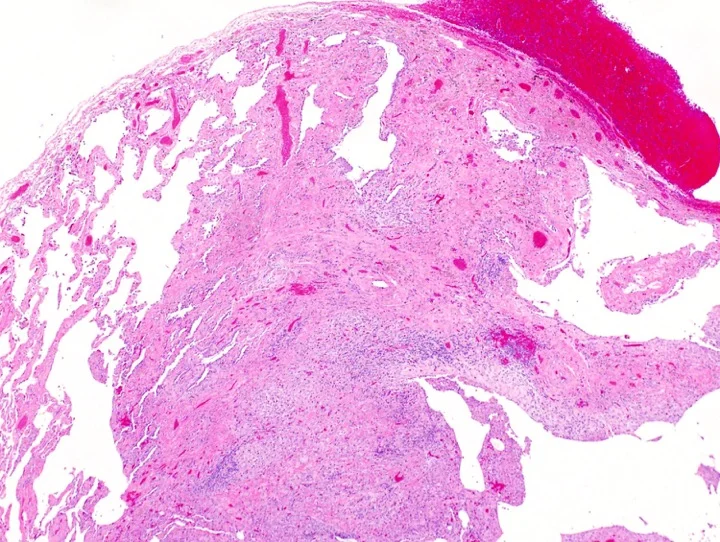

w/ Necrotizing Granulomas

Infection

Aspiration

GPA

Necrotizing Sarcoid